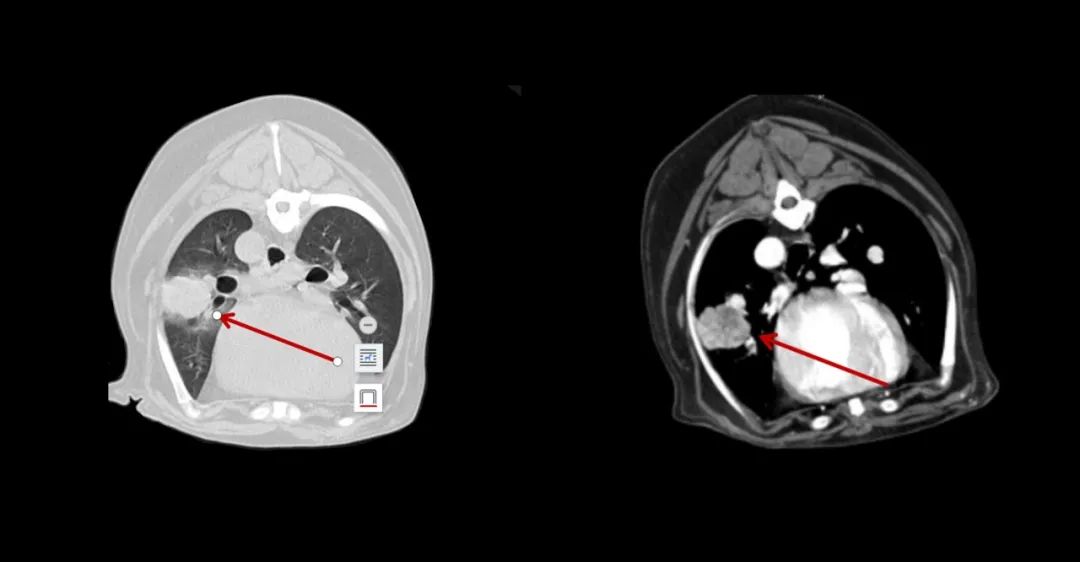

▲7歲成年犬,乳腺癌術后1年,發現肺部轉移。

▲寵物也喜歡吃燒烤,可惜竹簽卡在食道里了。